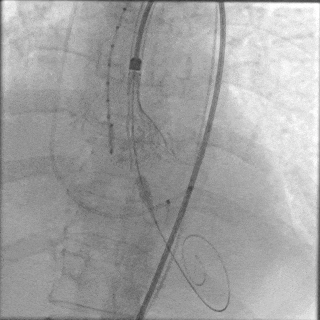

由于患者本身是Type0型二叶瓣,加上钙化较重,给瓣膜植入的位置增加了难度,术中释放多次释放部分回收后,最终释放一个比较满意的位置。

最终定位

最终释放

瓣膜稳步脱钩后,造影显示瓣膜位置合适,冠脉灌注良好,无瓣周漏。

稳步脱钩

最终造影